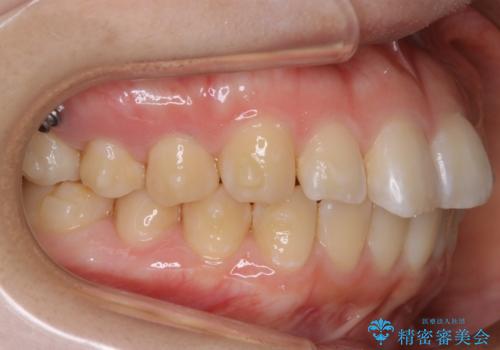

【非抜歯】ガタつきと歯軸を正して長持ちする歯へ

- 歯のガタつきと噛み合わせの改善を主訴に来院されました。

非抜歯で、少量の奥歯の移動と歯列の拡大・IPRを駆使して主訴を改善するための治療計画を立案しました。